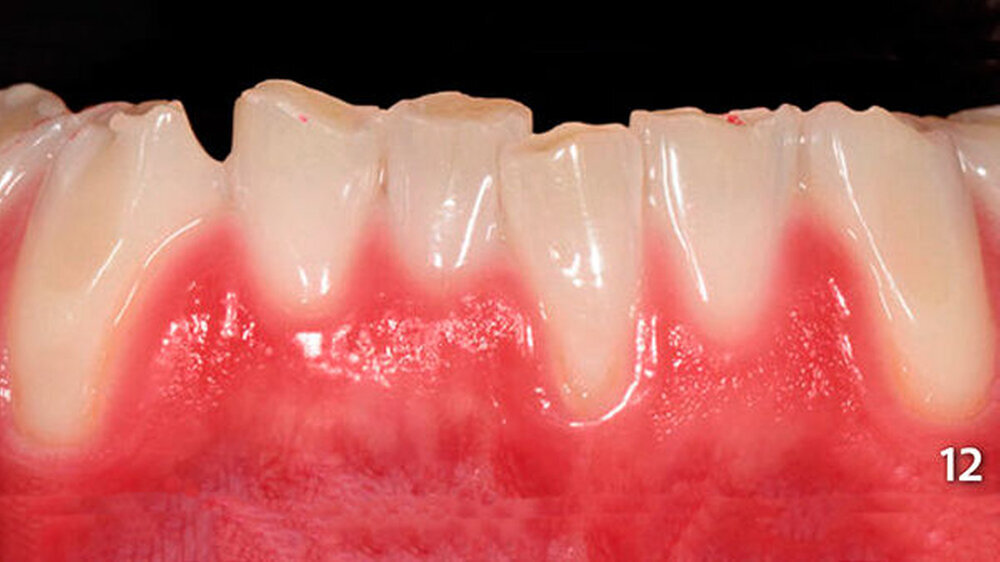

Die schwer zugänglichen Approximalflächen und -übergänge wurden mit oszillierenden, einseitig diamantierten Feilen (Proxo Shape Flexible, Fa. Intensiv, Grancia, Schweiz) ausgearbeitet und geglättet (Abb. 10). Mit dieser Technik wurden die Seitenzähne im Unterkiefer schrittweise aufgebaut und am Ende poliert (Abb. 11). Abschließend erfolgte die Versorgung der Frontzähne im Unterkiefer mit Komposit unter Verwendung der Bodymasse (Farbe A3B) des oben genannten Komposits (Abb. 12, 13).